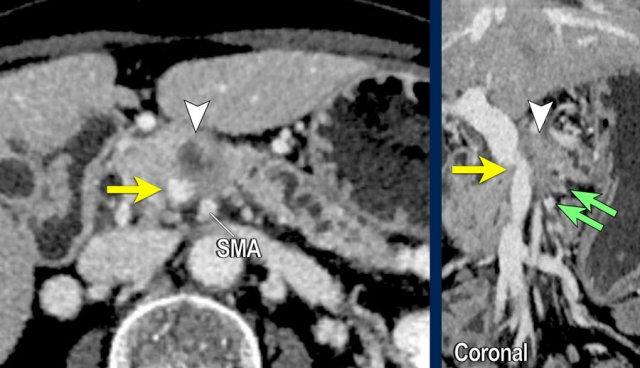

Việc sử dụng tái tạo đa mặt phẳng (multiplanar reformation) giúp cải thiện hiệu quả chẩn đoán tổng thể của CT, như được minh họa trong trường hợp này.

Tái tạo mặt phẳng coronal cho thấy một khối u nhỏ ở đầu tụy (đầu mũi tên) gây tắc nghẽn ống mật chủ.

Có vẻ chỉ có tiếp xúc hạn chế với tĩnh mạch cửa (mũi tên).

Tiếp tục xem các hình ảnh tiếp theo.

Tái tạo đa mặt phẳng vuông góc với tĩnh mạch cửa cho thấy mức độ tiếp xúc với tĩnh mạch cửa rộng hơn, từ 90 đến 180 độ (mũi tên).

Khi không có bất thường bờ viền, trường hợp này được phân loại là có thể cắt bỏ giới hạn (borderline resectable) theo tiêu chí DPCG, nhưng có thể cắt bỏ (resectable) theo tiêu chí NCCN.

Phẫu thuật cắt bỏ không kèm tái tạo tĩnh mạch cho kết quả R1, tức là có xâm lấn vi thể của khối u tại diện cắt.

Bất thường bờ viền mạch máu

CT axial cho thấy:

- Khối u ở thân tụy (đầu mũi tên trắng).

- Tiếp xúc khu trú < 90º với động mạch mạc treo tràng trên (SMA).

- Tiếp xúc rộng hơn từ 90º – 180º với SMV, SMV bị hẹp nhẹ và biến dạng (mũi tên vàng).

- Giãn ống tụy

Tái tạo mặt phẳng coronal cho thấy:

- Bất thường bờ viền thành SMV được nhận thấy rõ hơn trên tái tạo coronal này (mũi tên).

- Huyết khối trong các nhánh bên của SMV (mũi tên xanh nhỏ).